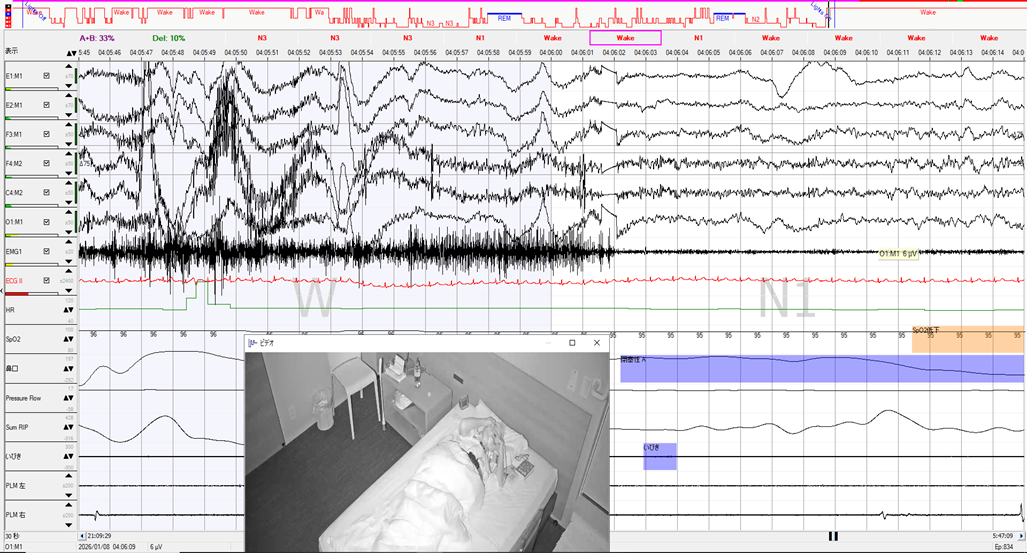

不眠を主訴に受診した中等度SAS症例

50歳台 男性 身長:180㎝ 体重:80 kg BMI:24.7 高血圧で通院中、家族からいびきと無呼吸を指摘され、高血圧との関連もありそうとのことで紹介受診されました。主訴は不眠で、23時に就床して、眠剤を服用しても朝4時ころまで寝付けないとのこと、簡易検査を施行した結果はREI=23.6で、診断PSGを行いました。結果はAHI=17.8回/時間と簡易検…